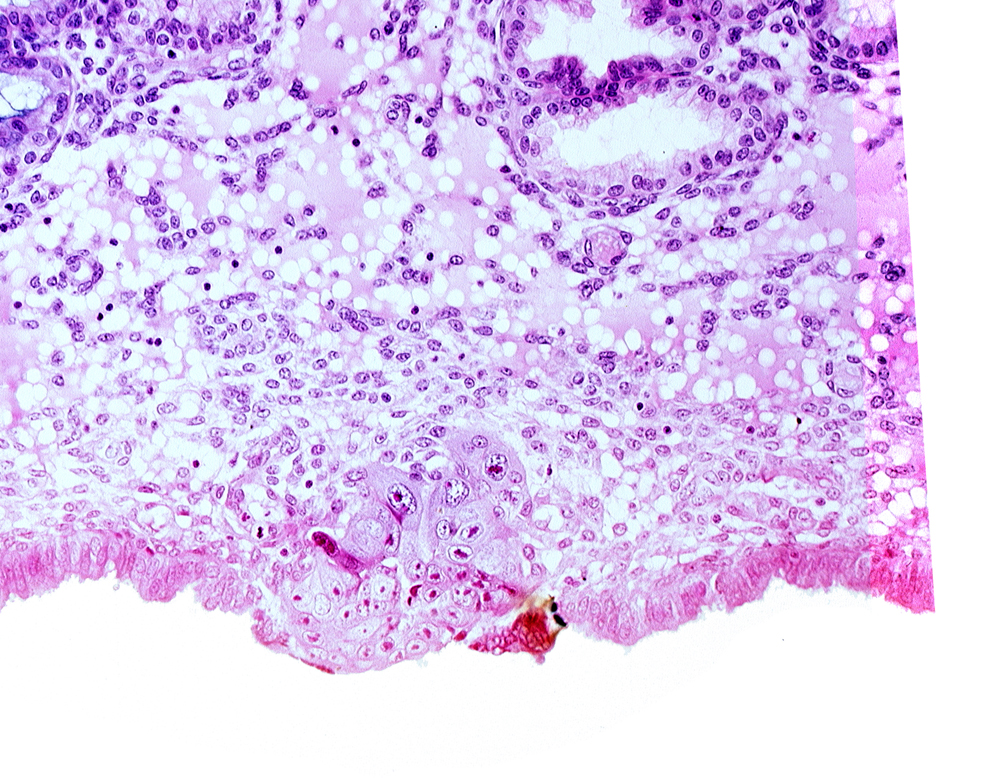

Carnegie Embryo #8155 | Location: 04-04-01

Keywords: cytotrophoblast, edematous endometrial stroma (decidua), endometrial epithelium, syncytiotrophoblast